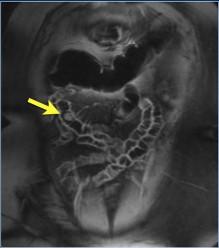

Lipome de intestin . Image TDM +

enteroclyse baryte une lipome de l'intestin (

en coupe frontale ) . Image ovalaire a hypodense a

bord lisse a distance de jejunum |